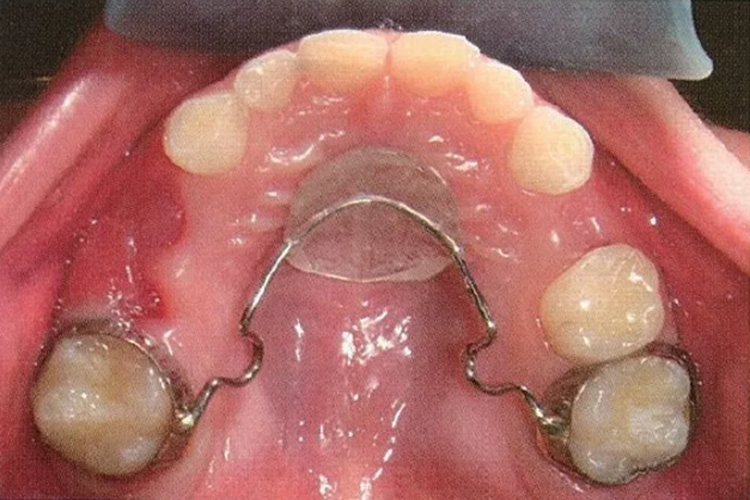

Nance弓间隙保持器

适用于上颌多颗后牙缺失的儿童。在双侧上颌第一恒磨牙或第二乳磨牙上粘接带环,并在舌侧焊接Nance弓基托抵住上腭前部,防止磨牙前移,需要注意上腭黏膜是否压迫损伤。